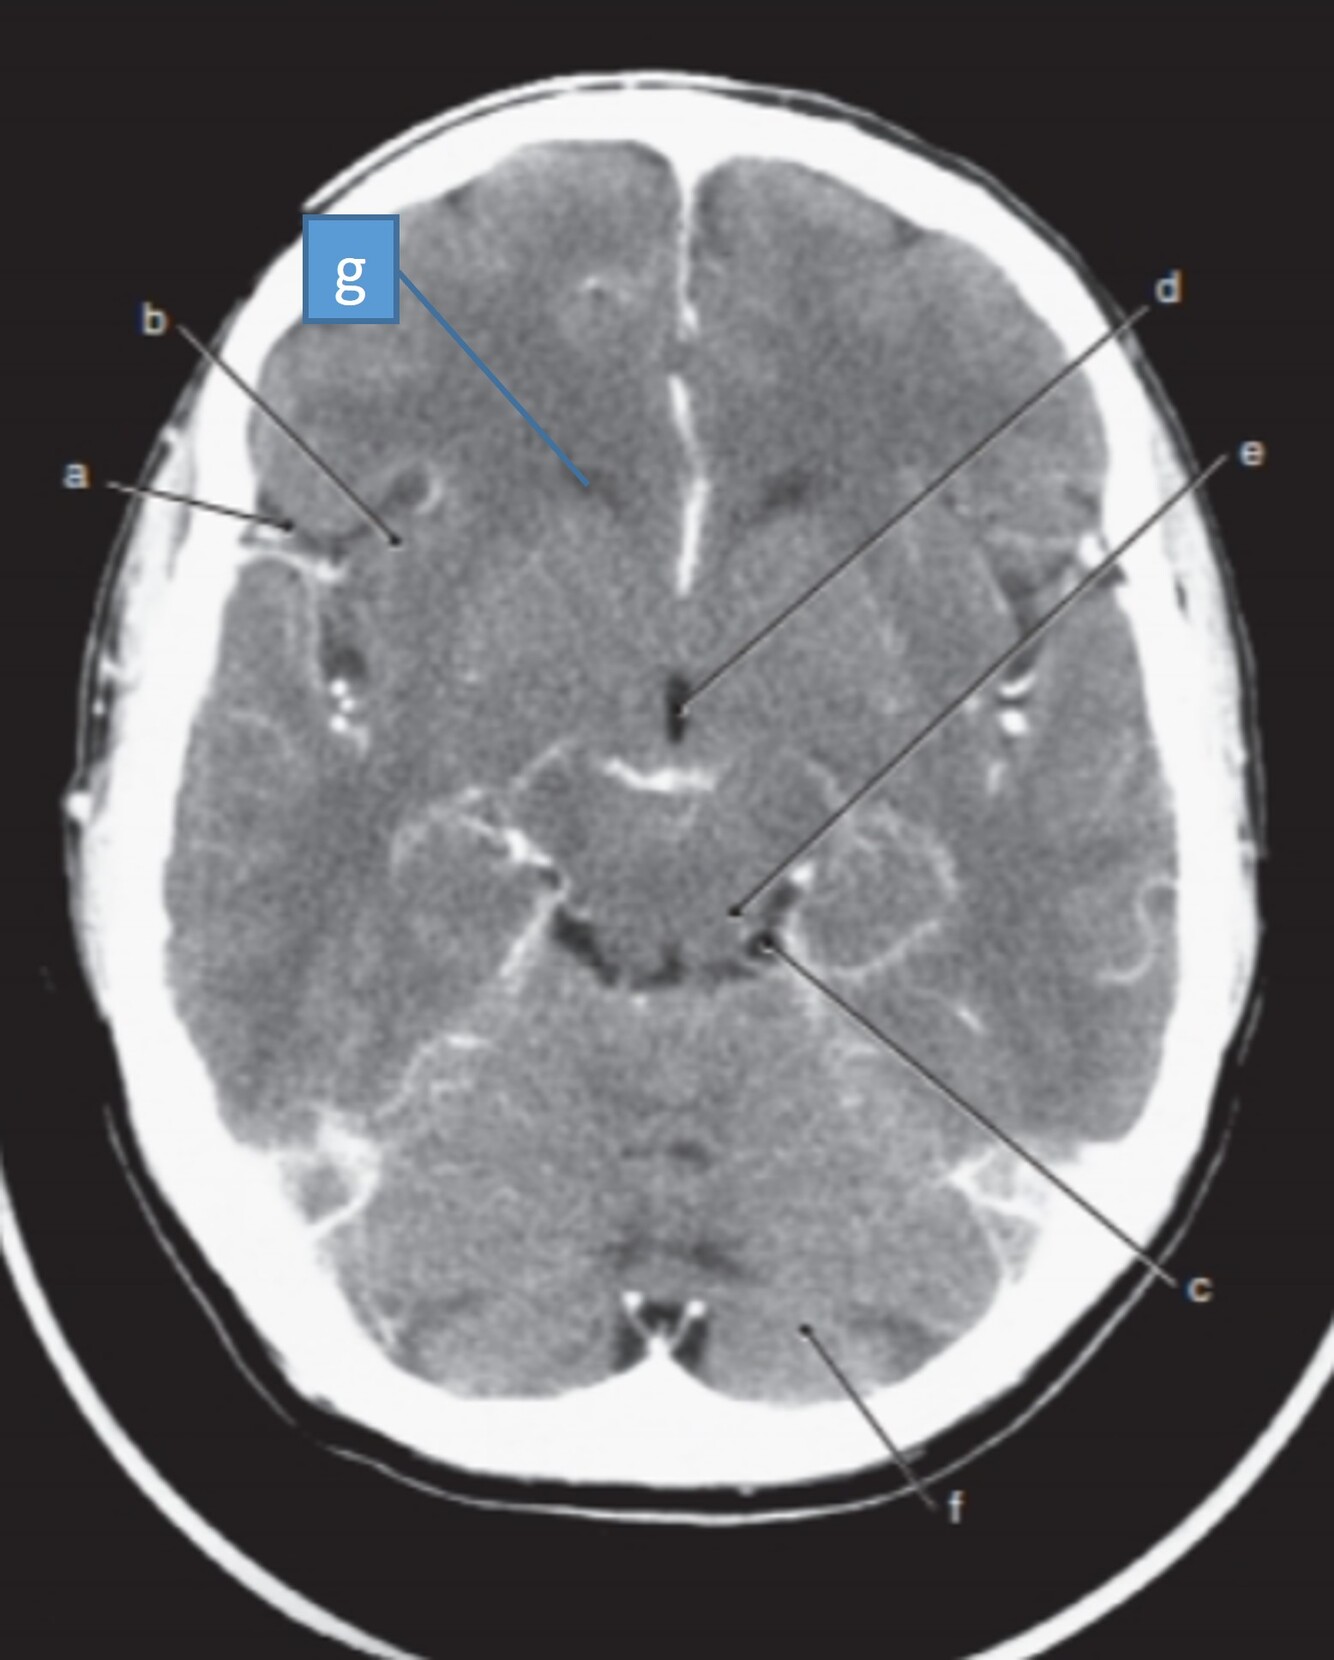

23

Label a,b,c,d,f,g

A

a-Rt lateral fissure

b=Insula

c=Quadrigeminal cistern

d-3rd ventricle

f-Cerebellum

g=Anterior horn (of rt lateral ventricle)